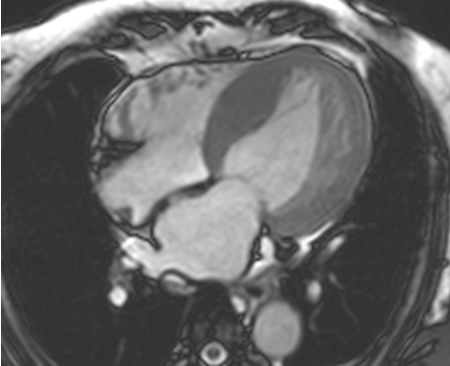

Estudos demonstraram que a RNMC tem uma elevada concordância com a ecocardiografia na medição de velocidades do fluxo de entrada mitral e velocidades de tecido do miocárdio, nos pacientes e controles.[73][74][Figure caption and citation for the preceding image starts]: Ressonância nuclear magnética cardíaca (RNMC) de paciente com infiltração amiloide cardíaca. Após injeção de contraste de gadolínio, na fase tardia há um anel basal subendocárdico no ventrículo esquerdo (corte de 4 câmaras)Do acervo de Dr Jessica Webb; usado com permissão [Citation ends].

[Figure caption and citation for the preceding image starts]: Ressonância nuclear magnética cardíaca (RNMC) de paciente com infiltração amiloide cardíaca. Após injeção de contraste de gadolínio, na fase tardia há um anel basal subendocárdico no ventrículo esquerdo (imagem de eixo curto basal)Do acervo de Dr Jessica Webb; usado com permissão [Citation ends].